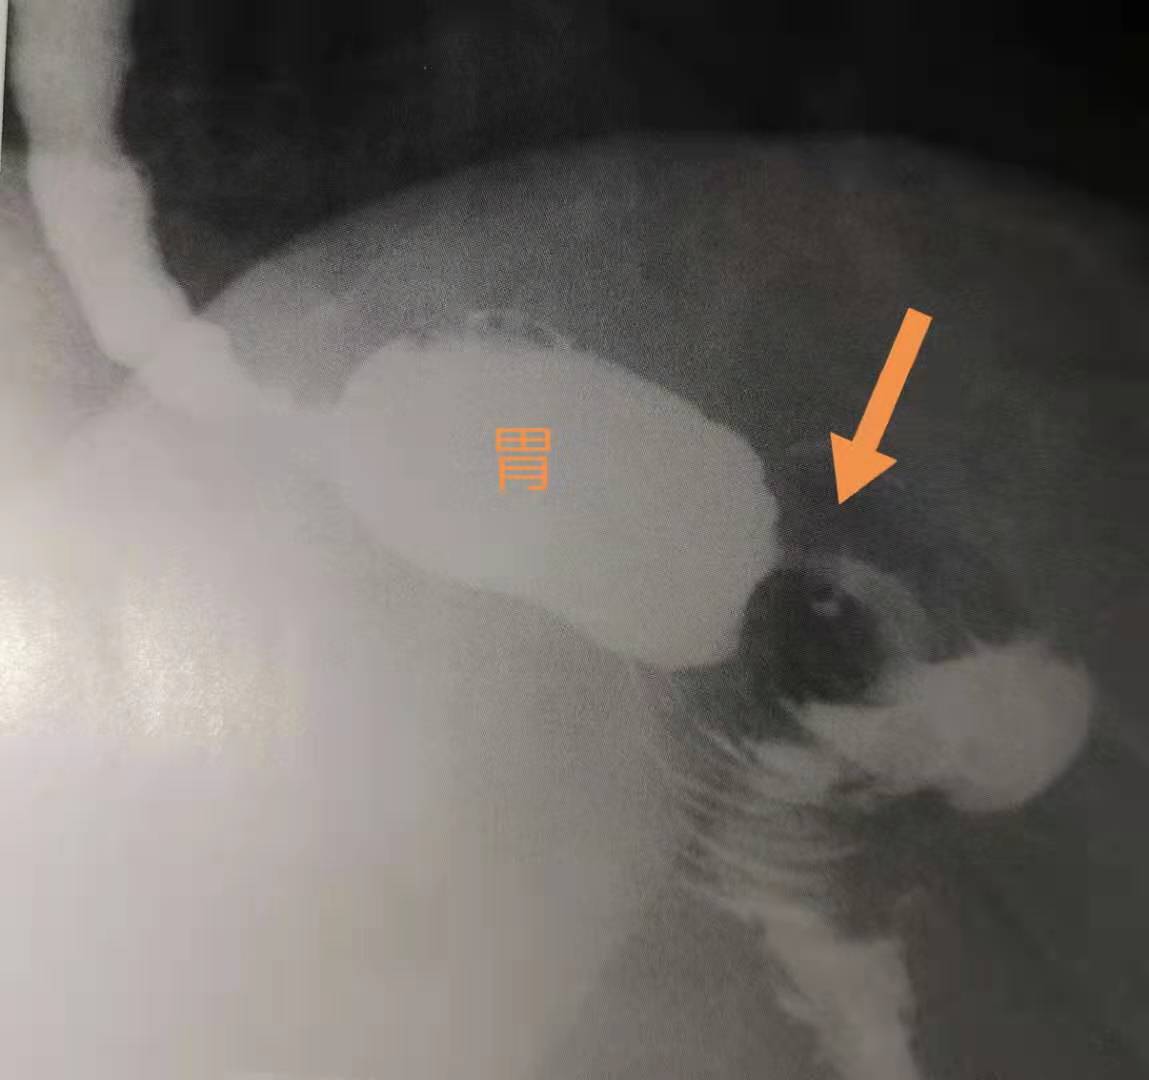

这位43岁的女士,就是手术3年后发生了吻合口狭窄,伴有局部溃疡形成,需要手术治疗。